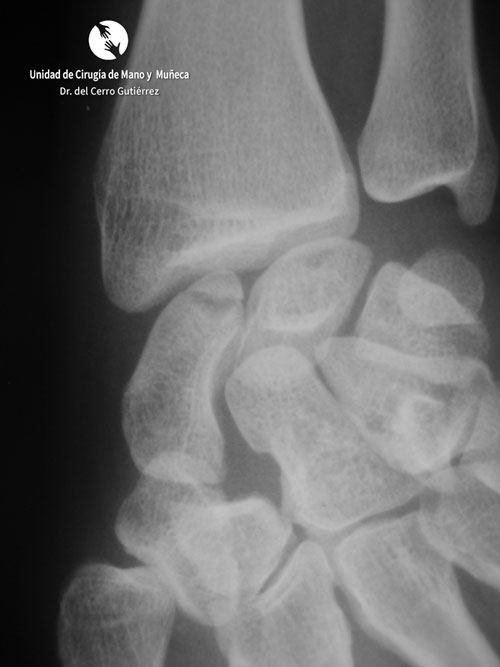

Pseudoartrosis. Inestabilidad Dorsal del Segmento Intermedio. DISI

Fractura del escafoides. Pseudoartrosis del tercio medio

Pseudoartrosis bilateral del escafoides